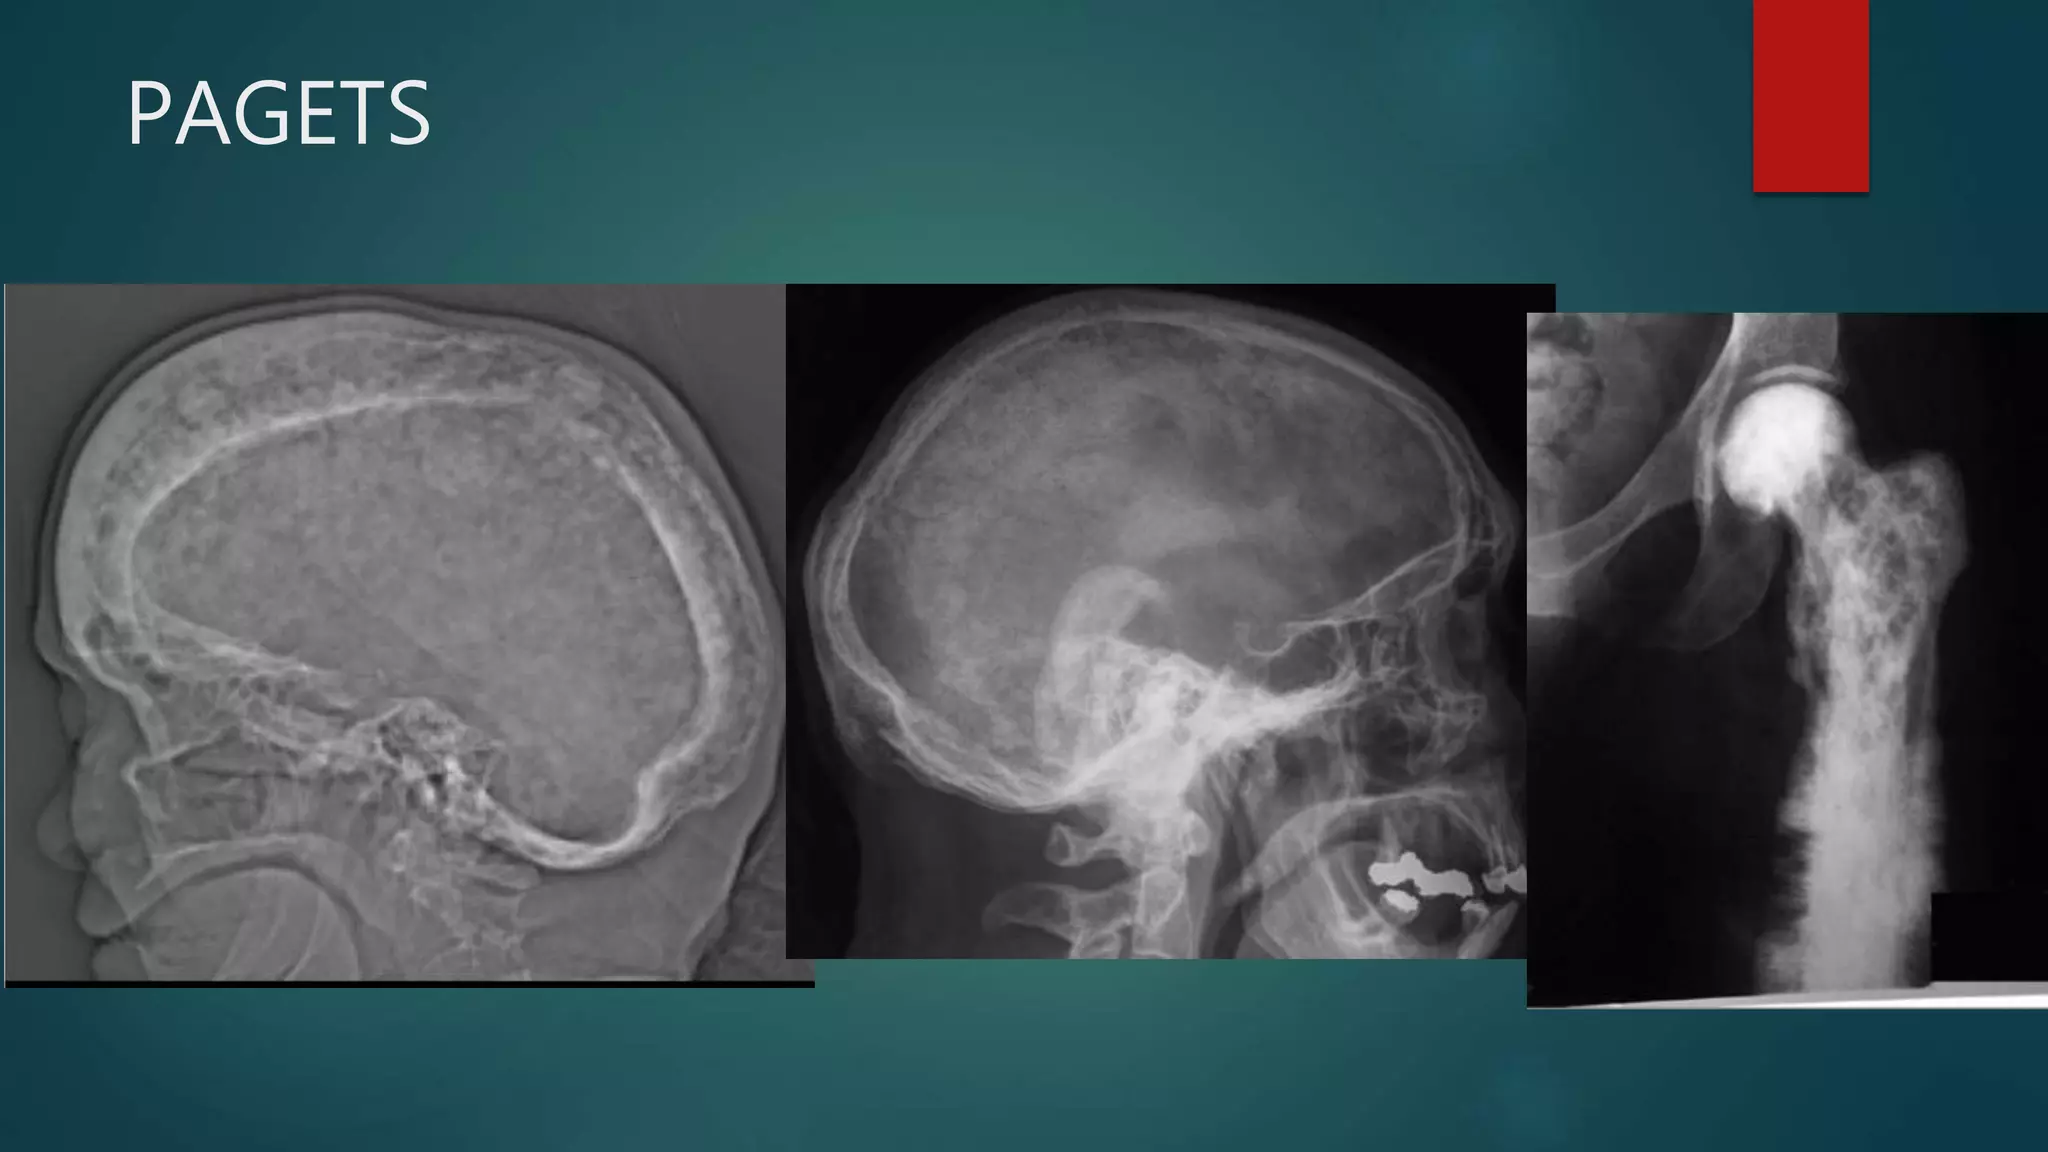

PAGETS

Signs of Paget’s disease

There are many Paget disease-related signs,

listed here and described in the modality-

specific sections below:

•banana fracture

•blade of grass sign

•cotton wool appearance of bone

•ivory vertebra sign

•jigsaw pattern bone or mosaic pattern bone

•Lincoln sign

•Looser zones

•Mickey Mouse sign

•osteoporosis circumscripta

•picture frame vertebra

•Tam o' Shanter sign

Fibrous Dysplasia

• #72 1.Paget involvement of the skull, with widening of the diploic space, typical "cotton wool" appearance and over-riding enlarged frontal bone (Tam o' Shanter sign). 2. Marked thickening of the calvarium. The diploic space is widened and there are ill-defined sclerotic and lucent areas throughout. The cortex is thickened and irregular. 3. Osteosarcoma in Paget disease